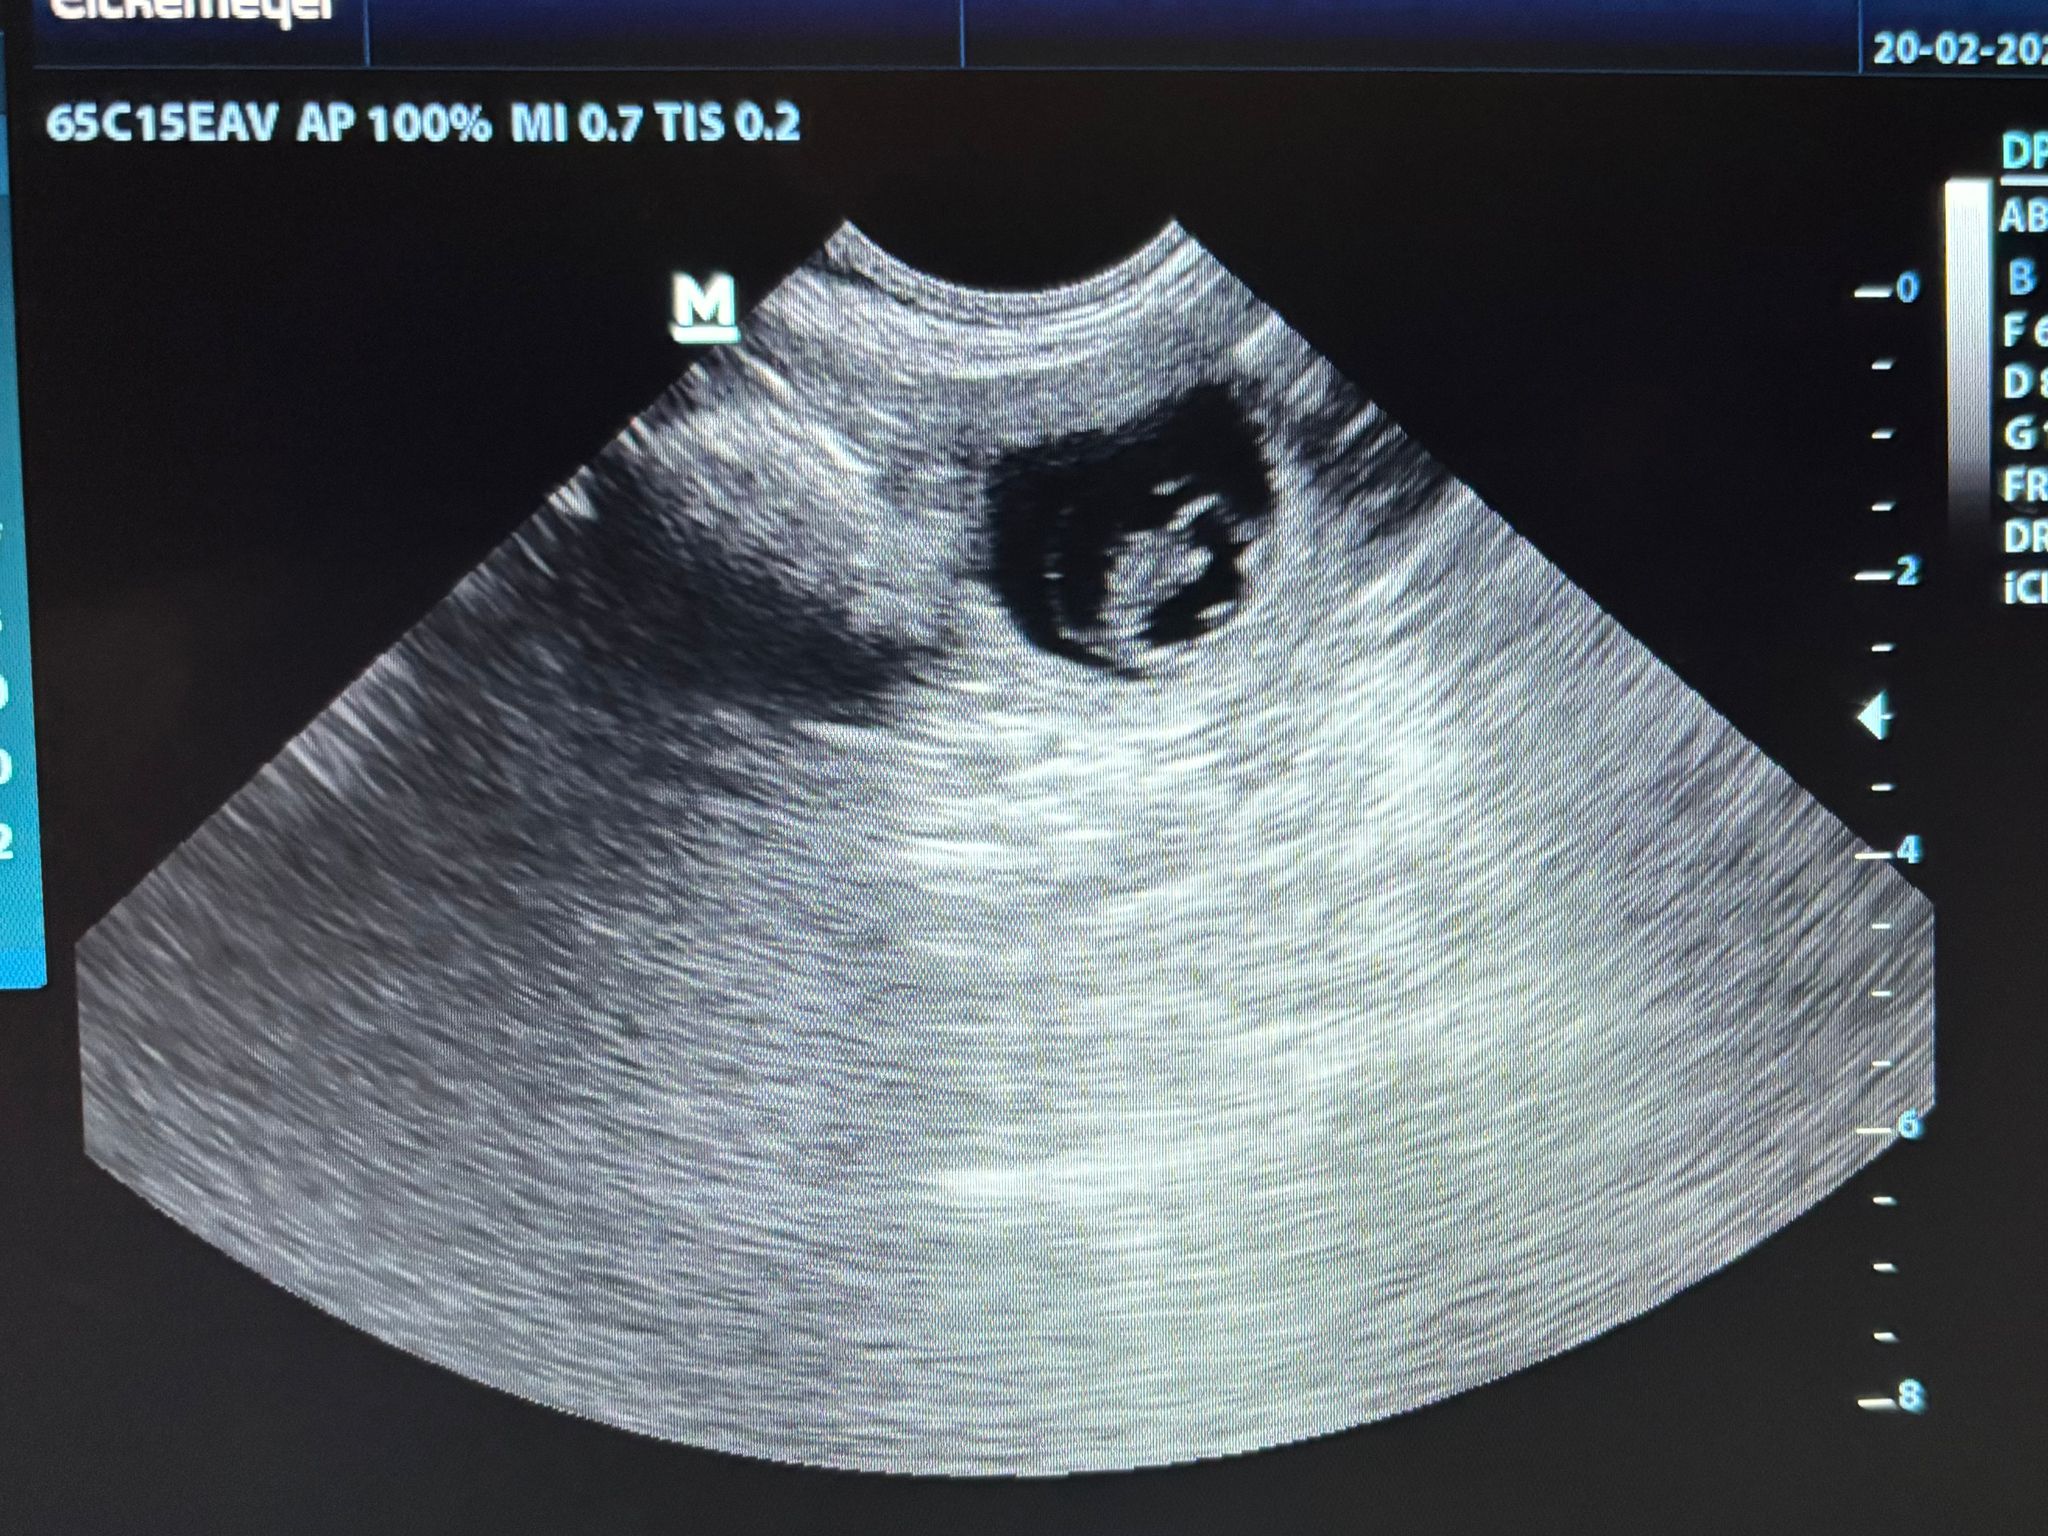

Beim Ultraschall bei unserer Tierärztin hat sich gestern Abend (19.2.2026) gezeigt, dass unsere Maite vom Nikolausberg nun trächtig ist und aus der Verpaarung mit unserem Duke Ellington kleine English Cocker Spaniel Welpen bekommen wird. Wir sind schon so gespannt auf den A-Wurf.

Am 26. März 2026 wäre der berechnete Wurftag aufgrund des 1. Deckakts. Der Ultraschall zeigt aber wohl, dass sie noch kleiner sind und ein späterer Deckakt wahrscheinlich dazu führte.